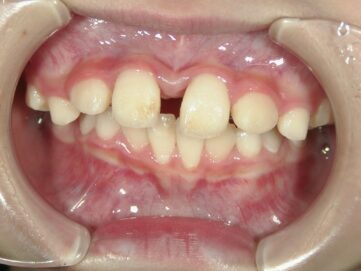

最近では歯並び・噛み合わせが悪い子供が増えてきています。成長期における生活環境や食生活による顎の成長不全が原因だと言われています。噛み合わせが悪いと歯がしっかりと生えることができなかったり、八重歯や出っ歯などの 不正咬合となってしまう可能性があります。

また、その他にも呼吸障害も誘発されたりなど、身体にも影響を及ぼします。これらは、顎骨の未発達が原因で起こる事が多いですが、小児期の矯正治療で治す事が可能です。

顎顔面矯正治療とは、歯並びだけでなく噛み合わせや顎関節を考慮して行う矯正治療のことです。顎顔面矯正治療により、顎関節症の緩和や鼻づまりの改善効果も期待できると言われています。主に、小児期に行い、見た目をよくするだけではなく、顎の骨や顔の骨格を正しい形に導きます。

歯並びの悪い原因としては顎の急な成長によるものが多く、装置で顎を広げる事で歯が綺麗に並ぶスペースを確保します。